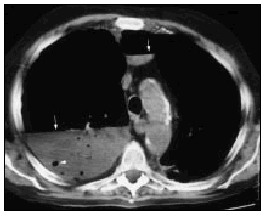

Varón de 60 años, diabético y con insuficiencia respiratoria crónica por enfisema pulmonar que ingresa por una neumonía en el lóbulo medio derecho. Se inició tratamiento con broncodilatadores inhalados, una cefalosporina de tercera generación y un macrólido, con mejoría inicial. En la tercera semana, ante la persistencia de cuadro febril, se realizó una radiografía de tórax (fig. 1) en la que se observa un infiltrado en el pulmón derecho de gran tamaño y con nivel hidroaéreo, por lo que se le añadió un antibiótico anaerobicida. En una TC torácica se observaba la lesión ya conocida (fig. 2. flecha izquierda) y otra pequeña imagen redondeada, con nivel hidroaéreo en su interior, en el espacio prevascular (fig. 2. flecha derecha). El fluido contenido en la lesión mayor era más denso que el agua y tenía burbujas de gas en su interior (fig. 2 punta de flecha). En un cultivo de esputo se cultivó Pseudomonas aeruginosa multisensible. Tras un acceso de tos, en una nueva radiografía de tórax (fig. 3) desaparece el infiltrado derecho, diseminándose la infección pulmonar, falleciendo el paciente días después en situación de shock séptico. Se estableció el siguiente diagnóstico: bullas pulmonares infectadas; bronconeumonía bilateral por P. aeruginosa.

Fig. 2.